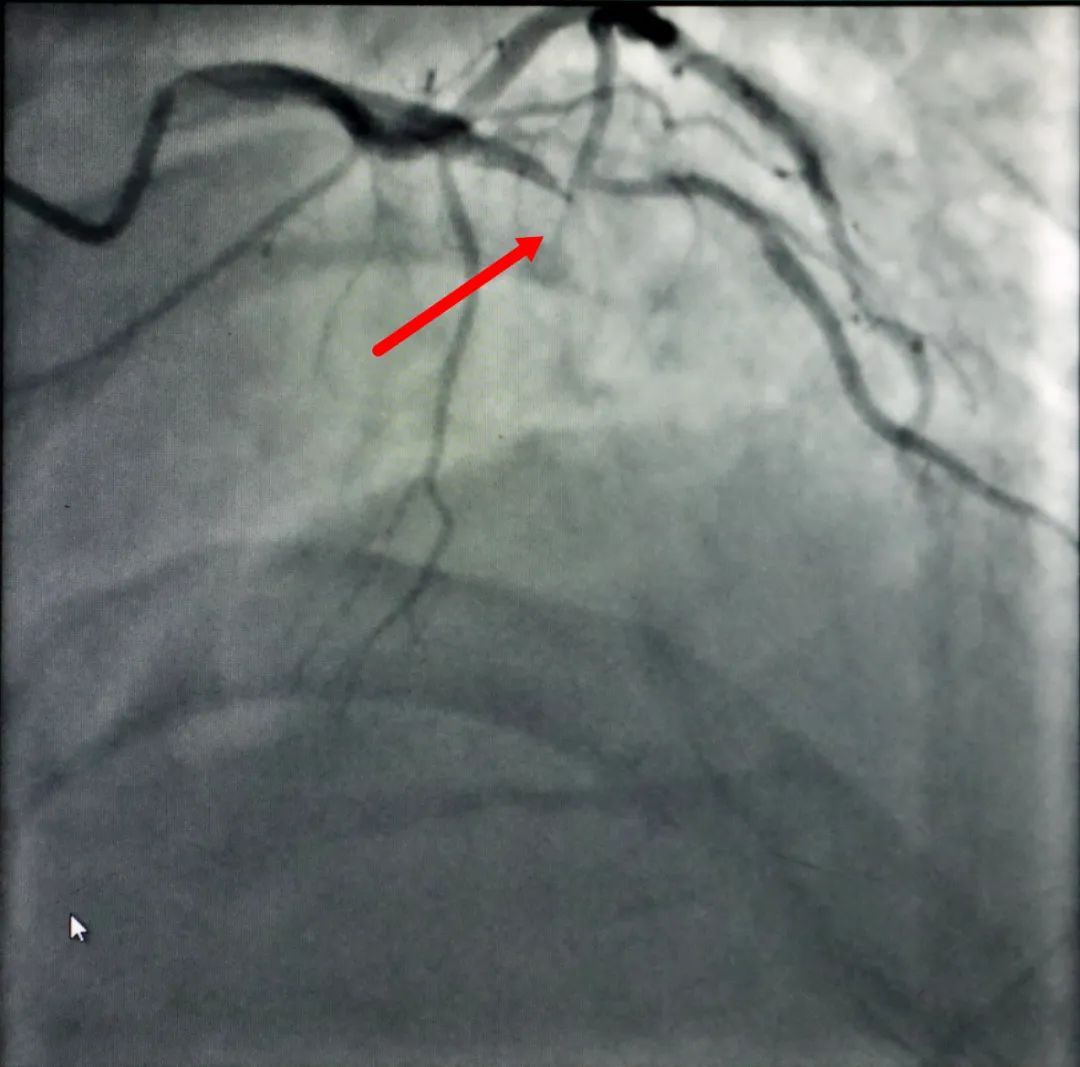

“立即电除颤”“快快快,赶紧心肺复苏”......随着一个个抢救指令不停的从病房内发出,一场与死神的正面“硬刚”随即展开。第一次电除颤很快让吴某恢复了窦性节律和意识,但紧接着,更可怕的情况发生了——心脏“电风暴”来袭,吴某的心脏几次“罢工”,室速、室颤一轮接一轮,险象环生,紧张的气氛弥漫在病房内,尽管汗水早已湿透了衣身,但医护人员仍全力以赴、分秒必争地坚持抢救,在医护人员的默契配合和不懈努力下,经过6次的除颤、心肺复苏后,“电风暴”终于平息下来。 支架植入前(左)和支架植入后(右) 姜同辉主任说:“抢救此类患者,紧急迅速开通血管最为关键!”虽然经除颤、心肺复苏等抢救,吴某的血压、心率得到了改善,但其病情仍未稳定,如再反复发生室颤必将危及生命。姜同辉主任立即将风险及治疗方案告知吴某及家属,征得同意后,迅速将吴某转入介入导管中心行急诊PCI(冠状动脉内支架植入术)治疗。结合病情,经冠脉造影术后,考虑前降支为此次急性心肌梗死“罪犯血管”,立即予吴某前降支植入支架,开通冠脉,改善心肌灌注。50分钟后手术成功,患者转入ICU进一步治疗。由于处置及时,术后吴某各项体征平稳,经一段时间的精心治疗,目前已康复出院。